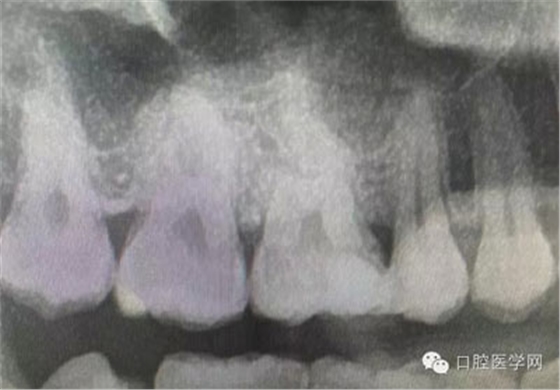

深齲或者是齲壞備洞的時(shí)候意外穿髓,我們?cè)趺刺幚砗眯??后期出現(xiàn)的牙髓的癥狀,是我們操作的問(wèn)題?比如細(xì)菌層的存在,我們沒有清理干凈?還是我們窩洞沒有進(jìn)行消毒,或者是隔濕沒有做好導(dǎo)致的粘結(jié)出現(xiàn)問(wèn)題,還是材料充填的時(shí)手法不對(duì),導(dǎo)致的材料收縮過(guò)大,還是我們的光照設(shè)備出現(xiàn)了老化沒有完全達(dá)到想要的固化,還是懸空的釉質(zhì)沒有去除導(dǎo)致的微滲漏的發(fā)生,或者是材料本身對(duì)牙髓產(chǎn)生的刺激,還是材料選擇的問(wèn)題,或者是我們對(duì)材料的性能和說(shuō)明沒有足夠的了解導(dǎo)致的,沒有按照材料的要求去做,還是我們自身對(duì)牙齒情況的判斷出現(xiàn)的問(wèn)題......

這是一例外院樹脂修復(fù)后十個(gè)月出現(xiàn)牙髓炎癥狀的患者。遇到這樣子的患者大家會(huì)怎么做,證明選擇,還有就是可做可不做治療的如何去平衡。